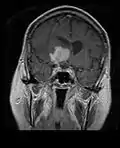

• MRI significantly underestimates extent of involvement; May appear focal on CT or MRI but parenchyma is typically diffusely involved.

• Intensely enhancing on MRI; may have a diffuse or “cotton wool” appearance on imaging.